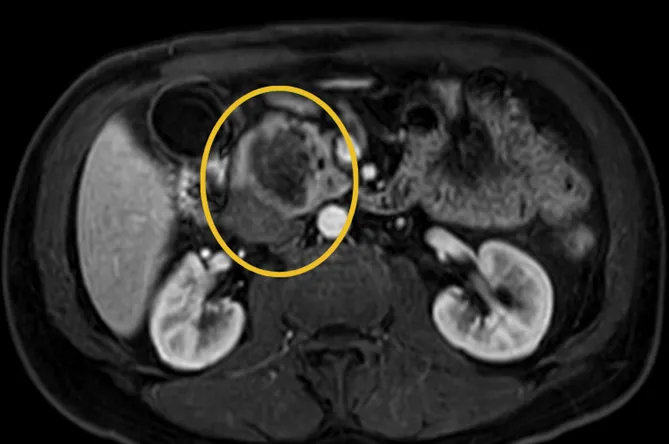

過去胰臟癌難以治癒的最大痛點在於「發現太晚」,台大醫院內科教授張毓廷簡報指出,主要是因為其位置深、多數無症狀、影像不明顯,早期幾乎無痛、無明顯症狀。